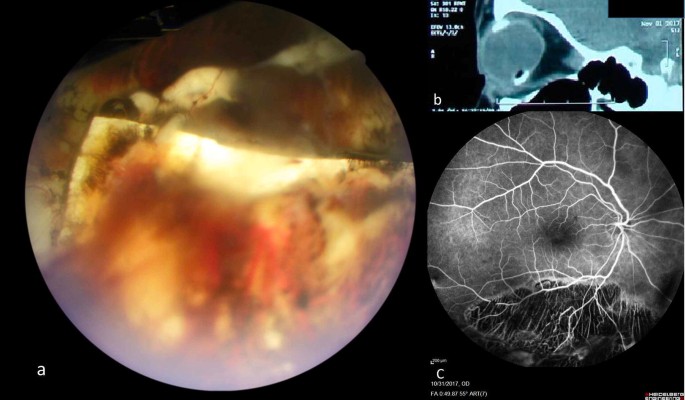

Close observation was scheduled. Partial resolution of haemorrhage revealed an intruded sponge segment in inferior vitreous cavity (Fig. 1a). To further clarify the pathology an orbital computed tomography was done (Fig. 1b). Fluorescein angiography was performed to rule out other causes of vitreous haemorrhage (Fig. 1c). To stabilize the retina as much as possible in case that buckle removal was needed, additional barrier laser was done. In following 16 months, despite multiple telephone recalls, patient did not comeback for followup visits. However, she reported good vision and no recurrence of symptoms.

Case 1: a An intruded silicone sponge, partially covered with blood is seen in inferior vitreous cavity. Adjacent retina and choroid show extensive pigmentary and atrophic changes. b In sagittal orbital computed tomography (CT) scan, intruded hypodense silicone sponge is seen over the hyper dense silicone rubber (tire and band complex) in inferior globe. c Fluorescein angiography shows an extensive hypofluorescent area caused by severe chorioretinal atrophy in inferior retina

Six patients had an encircling band combined with a segmental sponge (four cases) or a tire (two cases). A rubber tire is wider than a rubber band. Therefore, compared to a tightened band alone, force exerted by a tightened band on a tire is distributed over a larger area of sclera. This mechanism leads to decreased pressure over the underlying sclera and may be protective against erosion/intrusion [6]. Interestingly, in one of two reported cases with encircling band and a segmental tire, the intruded element has been the band in the “opposite quadrant” of the segmental tire [12]. Second reported case of combined encircling band and tire is case 1 of our report, who had reminiscences of excessive surgical interventions: placing a segmental sponge over the break after cryopexy, cryopexy and suturing of the drainage site, and using encircling tire and band over the sponge. Widespread atrophic changes in fluorescein angiography in this case (Fig. 1c) also suggests excessive cryopexy. This suggests that in cases of compromised scleral resistance- either as a preexisting condition or as a consequence of destructive surgical interventions-the tire may not be enough to protect the sclera from pressure of a tightened encircling band.